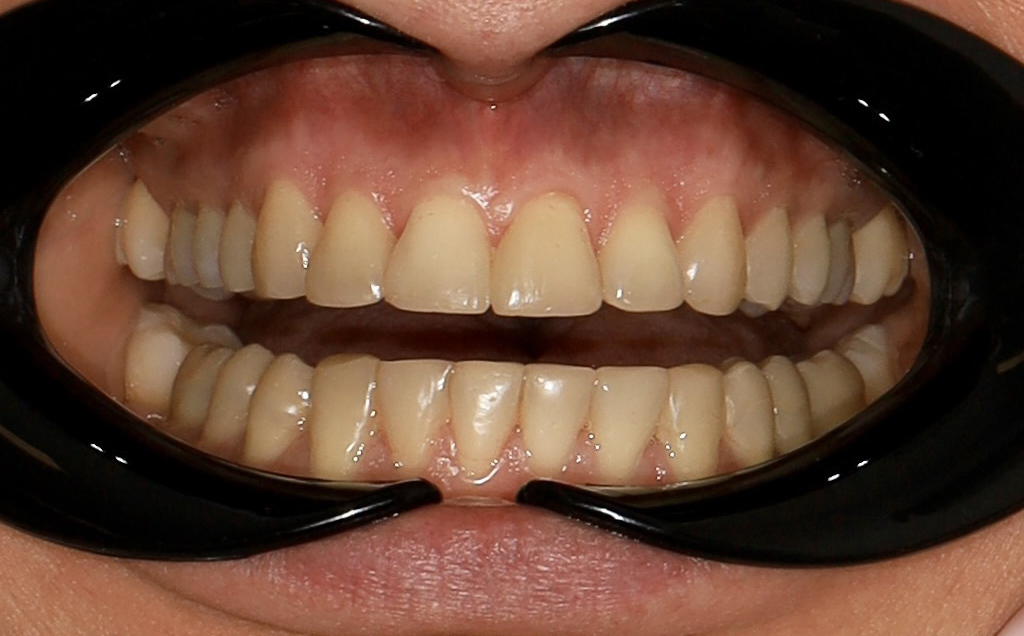

Zaprezentujemy serię poruszających historii pacjentów, którzy zdecydowali się na kompleksowe leczenie dentystyczne. Od przypadków zaawansowanej próchnicy, przez wypadki, które wymagały rekonstrukcji zębów, po pacjentów marzących o hollywoodzkim uśmiechu dzięki zastosowaniu licówek – każda historia jest dowodem na to, jak nowoczesna stomatologia może odmienić życie.

Skupimy się na innowacyjnych technologiach i metodach leczenia stosowanych w naszej klinice, które sprawiają, że te metamorfozy są możliwe. Od cyfrowego projektowania uśmiechu (DSD), przez ortodoncję i implanty, po zaawansowaną chirurgię szczękowo-twarzową. Omówimy, jak te techniki pracują razem, aby osiągnąć najlepsze wyniki.

Metamorfoza uśmiechu: usunięcie przebarwień i kamienia nazębnego.